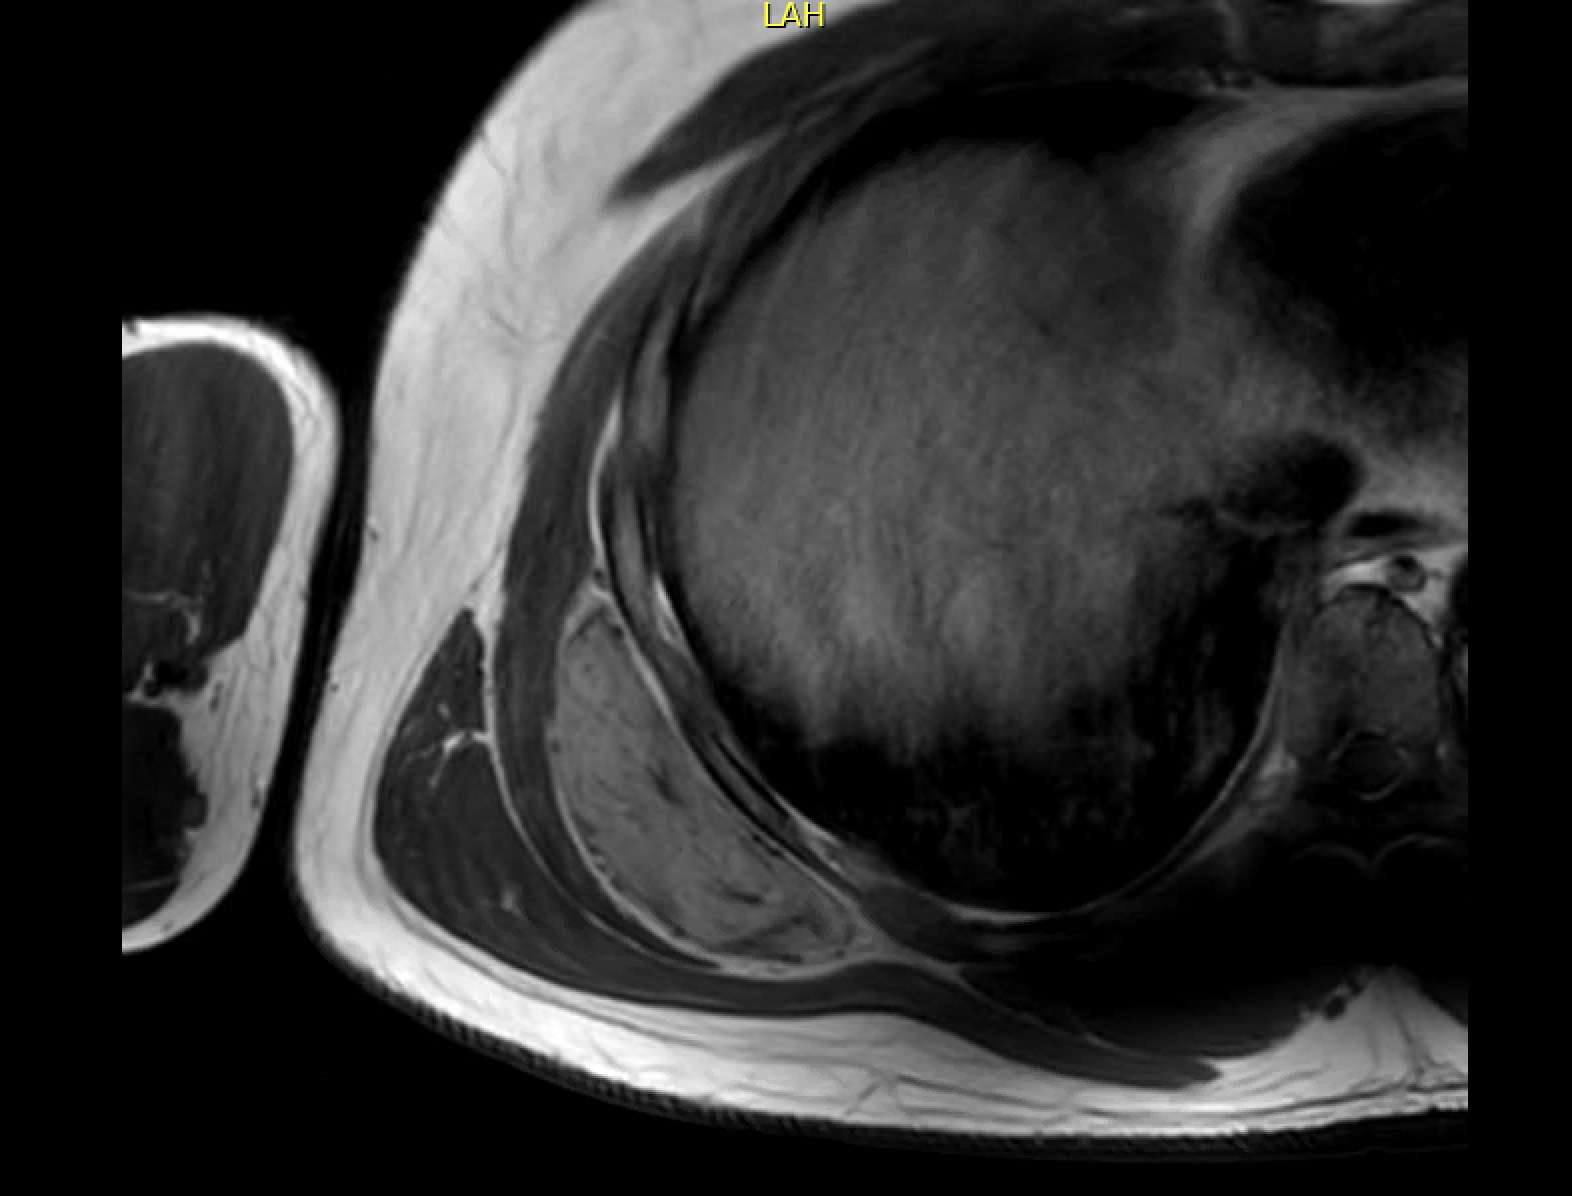

MRI

Semilunar, soft tissue mass abutting the rib cage posteriorly with well defined margins

Similar signal intensity to muscle